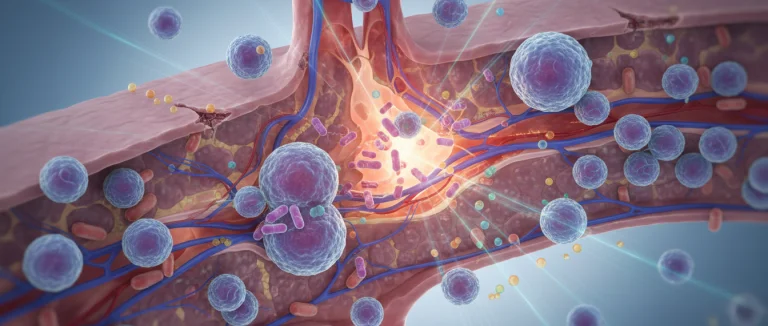

плюрипотентные гемопоэтические стволовые клетки

плюрипотентные клетки

плюрипотентные стволовые клетки

процедура стволовых клеток